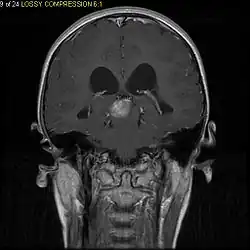

Stereotactic MRI brain scan showing a recurrent postoperative brain stem cystic pilocytic astrocytoma.